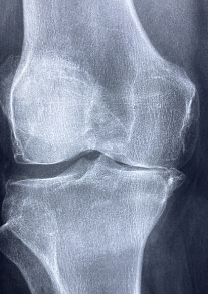

무릎 관절에 좋은 운동 및 무릎 관절에 관한 정보를 알아보도록 하겠습니다. 관절은 뼈와 뼈 사이에 위치하며, 뼈가 서로 움직일 수 있도록 돕는 유연한 연결부입니다. 관절은 뼈의 움직임을 통제하고 충격을 흡수하는 역할을 하며, 인체의 움직임과 자세를 유지하는 데 중요한 역할을 합니다. 관절에는 다양한 종류가 있으며, 골관절, 연골관절, 다발성 연골관절 등이 있습니다. 관절에는 연골, 인대, 근육, 건초 등이 있으며, 이러한 부위들은 관절 기능의 원활한 유지를 위해 균형을 유지하고 있습니다. 관절은 일상적인 활동과 운동에 필수적이며, 체중 관리, 근력 강화 등의 생활 습관을 통해 건강한 관절을 유지할 수 있습니다.

1. 무릎 안쪽 통증: 무릎 안쪽 통증은 보통 내측 반월상 연골 손상, 내측 인대 손상, 골관절염 등에 의해 발생합니다. 내측 반월상 연골은 무릎 관절의 안쪽 부분에 있는 연골로, 무릎 관절의 충격을 흡수하고 안정성을 유지하는 역할을 합니다. 내측 인대는 무릎 관절의 안쪽 부분에 있는 인대로, 무릎 관절의 좌우로 흔들리는 것을 방지하는 역할을 합니다. 골관절염은 무릎 관절의 연골이 마모되어 뼈와 뼈가 서로 부딪치는 질환으로, 나이가 들거나 비만, 과도한 운동 등에 의해 발생합니다.

2. 무릎 바깥쪽 통증: 무릎 바깥쪽 통증은 보통 외측 반월상 연골 손상, 외측 인대 손상, 근막통 증후군 등에 의해 발생합니다. 외측 반월상 연골은 무릎 관절의 바깥쪽 부분에 있는 연골로, 내측 반월상 연골과 같은 기능을 합니다. 외측 인대는 무릎 관절의 바깥쪽 부분에 있는 인대로, 내측 인대와 같은 기능을 합니다. 근막통 증후군은 근막이라는 근육을 감싸고 있는 조직이 염증을 일으키는 질환으로, 과도한 운동, 자세 장애, 스트레스 등에 의해 발생합니다.

3. 무릎 앞쪽 통증: 무릎 앞쪽 통증은 보통 전십자 인대 손상, 후방 경골연골염, 승모근 건염 등에 의해 발생합니다. 전십자 인대는 무릎 관절의 앞쪽 부분에 있는 인대로, 무릎 관절의 전후로 움직이는 것을 제어하는 역할을 합니다. 후방 경골연골염은 무릎 관절의 앞쪽 부분에 있는 경골이라는 뼈와 연골 사이에 염증이 생기는 질환으로, 자주 앉았다 일어서거나 계단을 오르내리는 등의 활동에 의해 발생합니다. 승모근 건염은 승모근이라는 근육과 건이라는 인대가 염증을 일으키는 질환으로, 과도한 운동, 자세 장애, 비정상적인 발목 운동 등에 의해 발생합니다.

4. 무릎 뒤쪽 통증: 무릎 뒤쪽 통증은 보통 후십자 인대 손상, 유착 인대 손상, Baker 낭종 등에 의해 발생합니다. 후십자 인대는 무릎 관절의 뒤쪽 부분에 있는 인대로, 전십자 인대와 같은 기능을 합니다. 유착 인대는 무릎 관절의 뒤쪽 부분에 있는 인대로, 무릎 관절의 회전을 제어하는 역할을 합니다. Baker 낭종은 무릎 관절의 뒤쪽 부분에 있는 점액낭이라는 부대형 구조물이 팽창하거나 파열되는 질환으로, 골관절염, 류마티스 관절염 등의 염증성 질환에 의해 발생합니다.

5. 무릎 전체 통증: 무릎 전체 통증은 보통 감염성 관절염, 류마티스 관절염, 활액 결핍 등에 의해 발생합니다. 감염성 관절염은 세균, 바이러스, 균류 등의 병원체가 무릎 관절에 침입하여 염증을 일으키는 질환으로, 고열, 붓기, 발적, 통증 등의 증상이 나타납니다. 류마티스 관절염은 면역 체계가 자신의 조직을 공격하여 염증을 일으키는 질환으로, 아침에 일어날 때 가장 심한 통증과 경직감이 나타납니다. 활액 결핍은 무릎 관절에 있는 활액이라는 점액질의 액체가 감소하여 연골이 마모되고 통증이 발생하는 질환으로, 나이가 들거나 비만, 과도한 운동 등에 의해 발생합니다.

1. 연골 손상: 연골은 뼈와 뼈 사이에 있는 부드러운 조직으로, 충격을 흡수하고 마찰을 줄여주는 역할을 합니다. 연골이 손상되면 뼈와 뼈가 서로 부딪치면서 통증이 생길 수 있습니다. 연골 손상의 원인은 나이가 들면서 자연적으로 연골이 닳거나, 스포츠나 사고 등으로 인한 외부적인 충격입니다.

3. 관절염: 관절염은 관절에 염증이 생기는 질환으로, 다양한 종류가 있습니다. 대표적인 예로는 류마티스 관절염, 골관절염, 강직성 척추염 등이 있습니다. 관절염은 관절에 붓기, 따끔거림, 열감, 움직임 제한 등의 증상을 일으킵니다.